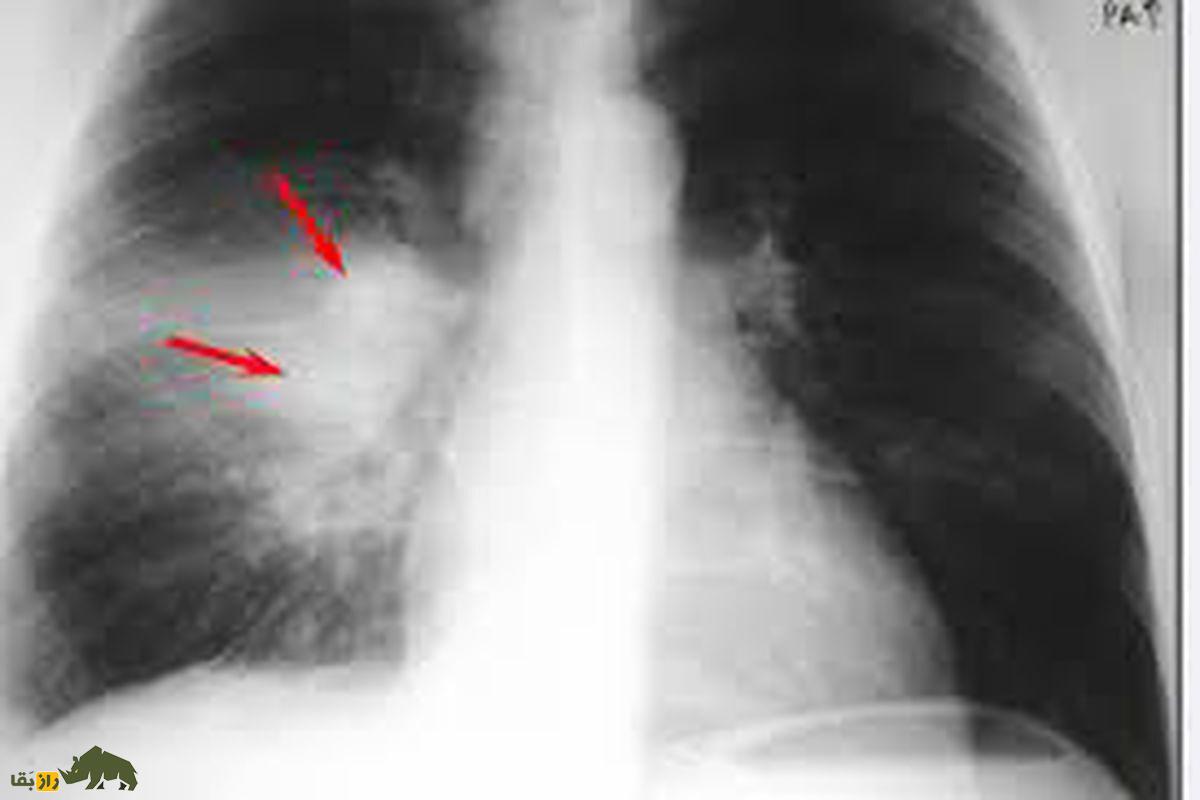

سل که توسط باکتری Mycobacterium tuberculosis ایجاد میشود، بیماریای قابل درمان است که اگر بهموقع تشخیص داده نشود، جان نیمی از مبتلایان را میگیرد.